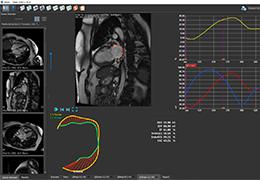

ANYTHINK 经导管主动脉瓣膜置换术分析系统